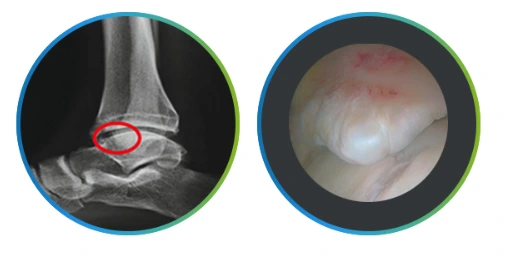

골성충돌증후군

골성충돌증후군.PNG

골성, 그러니까 골극으로 인해 염증이 생기는 충돌증후군으로 연부조직이 골극과 관절 사이를 압박하는 질환입니다.

다만 골극 자체가 통증을 발생시키는 것은 아니라 발목 전방에 형성된 골극 때문에 발생합니다 발목관절을 최대학 족저굴곡시키는 자세를 반복할 경우 견인 골곡이 형성되며 이로 인한 염증으로 인해 통증이 발생합니다.